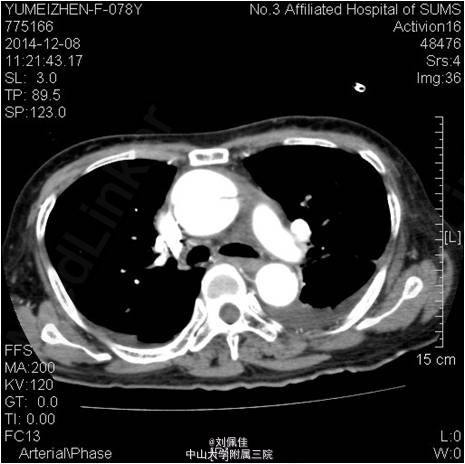

入院后多次复查心梗三项均为阴性。心电图与入院相较变化不大。入院:WBC 13x10e9/L,HGB 85g(小细胞低色素),ESR:45.00mm/H;CRP:153.200mg/L;白蛋白28.800g/L。CA125 90U/ml。转氨酶、BUN、Cr正常。血清LDH 285U/L。 床旁心脏彩提示:心包积液。予以心包穿刺抽液。 患者活动后胸闷、气促由心包积液所引起,暂不考虑急性冠脉综合征,停用抗血小板、抗凝药物。予可乐必妥抗感染、护胃、营养心肌、通便、镇静安眠、心包引流等治疗。 2014-12-8日行胸部CT提示:主动脉夹层(Debakey II型),并血栓形成。请介入科会诊,介入科医师会诊,建议转至外院心胸外科行手术治疗Stanford A型主动脉夹层。与患者家属沟通后,患者签字拒绝手术,表示愿意接受内科保守治疗。 予加用康忻5mgQd控制心率在60-70bpm,硝普钠控制血压在100/60mmHg左右。根据患者血压、心率情况,逐渐调整药物,现予康忻5mgBid,蒙诺5mgQd治疗,血压波动在95-115/55-65mmHg,HR 75-90bpm。 患者入院后偶有心前区、季肋部刺痛,阵发性,考虑与心包摩擦相关。未诉腹痛、背痛,未出现明显撕裂样疼痛。住院期间病情尚平稳,未发现夹层进一步撕裂的临床表现。